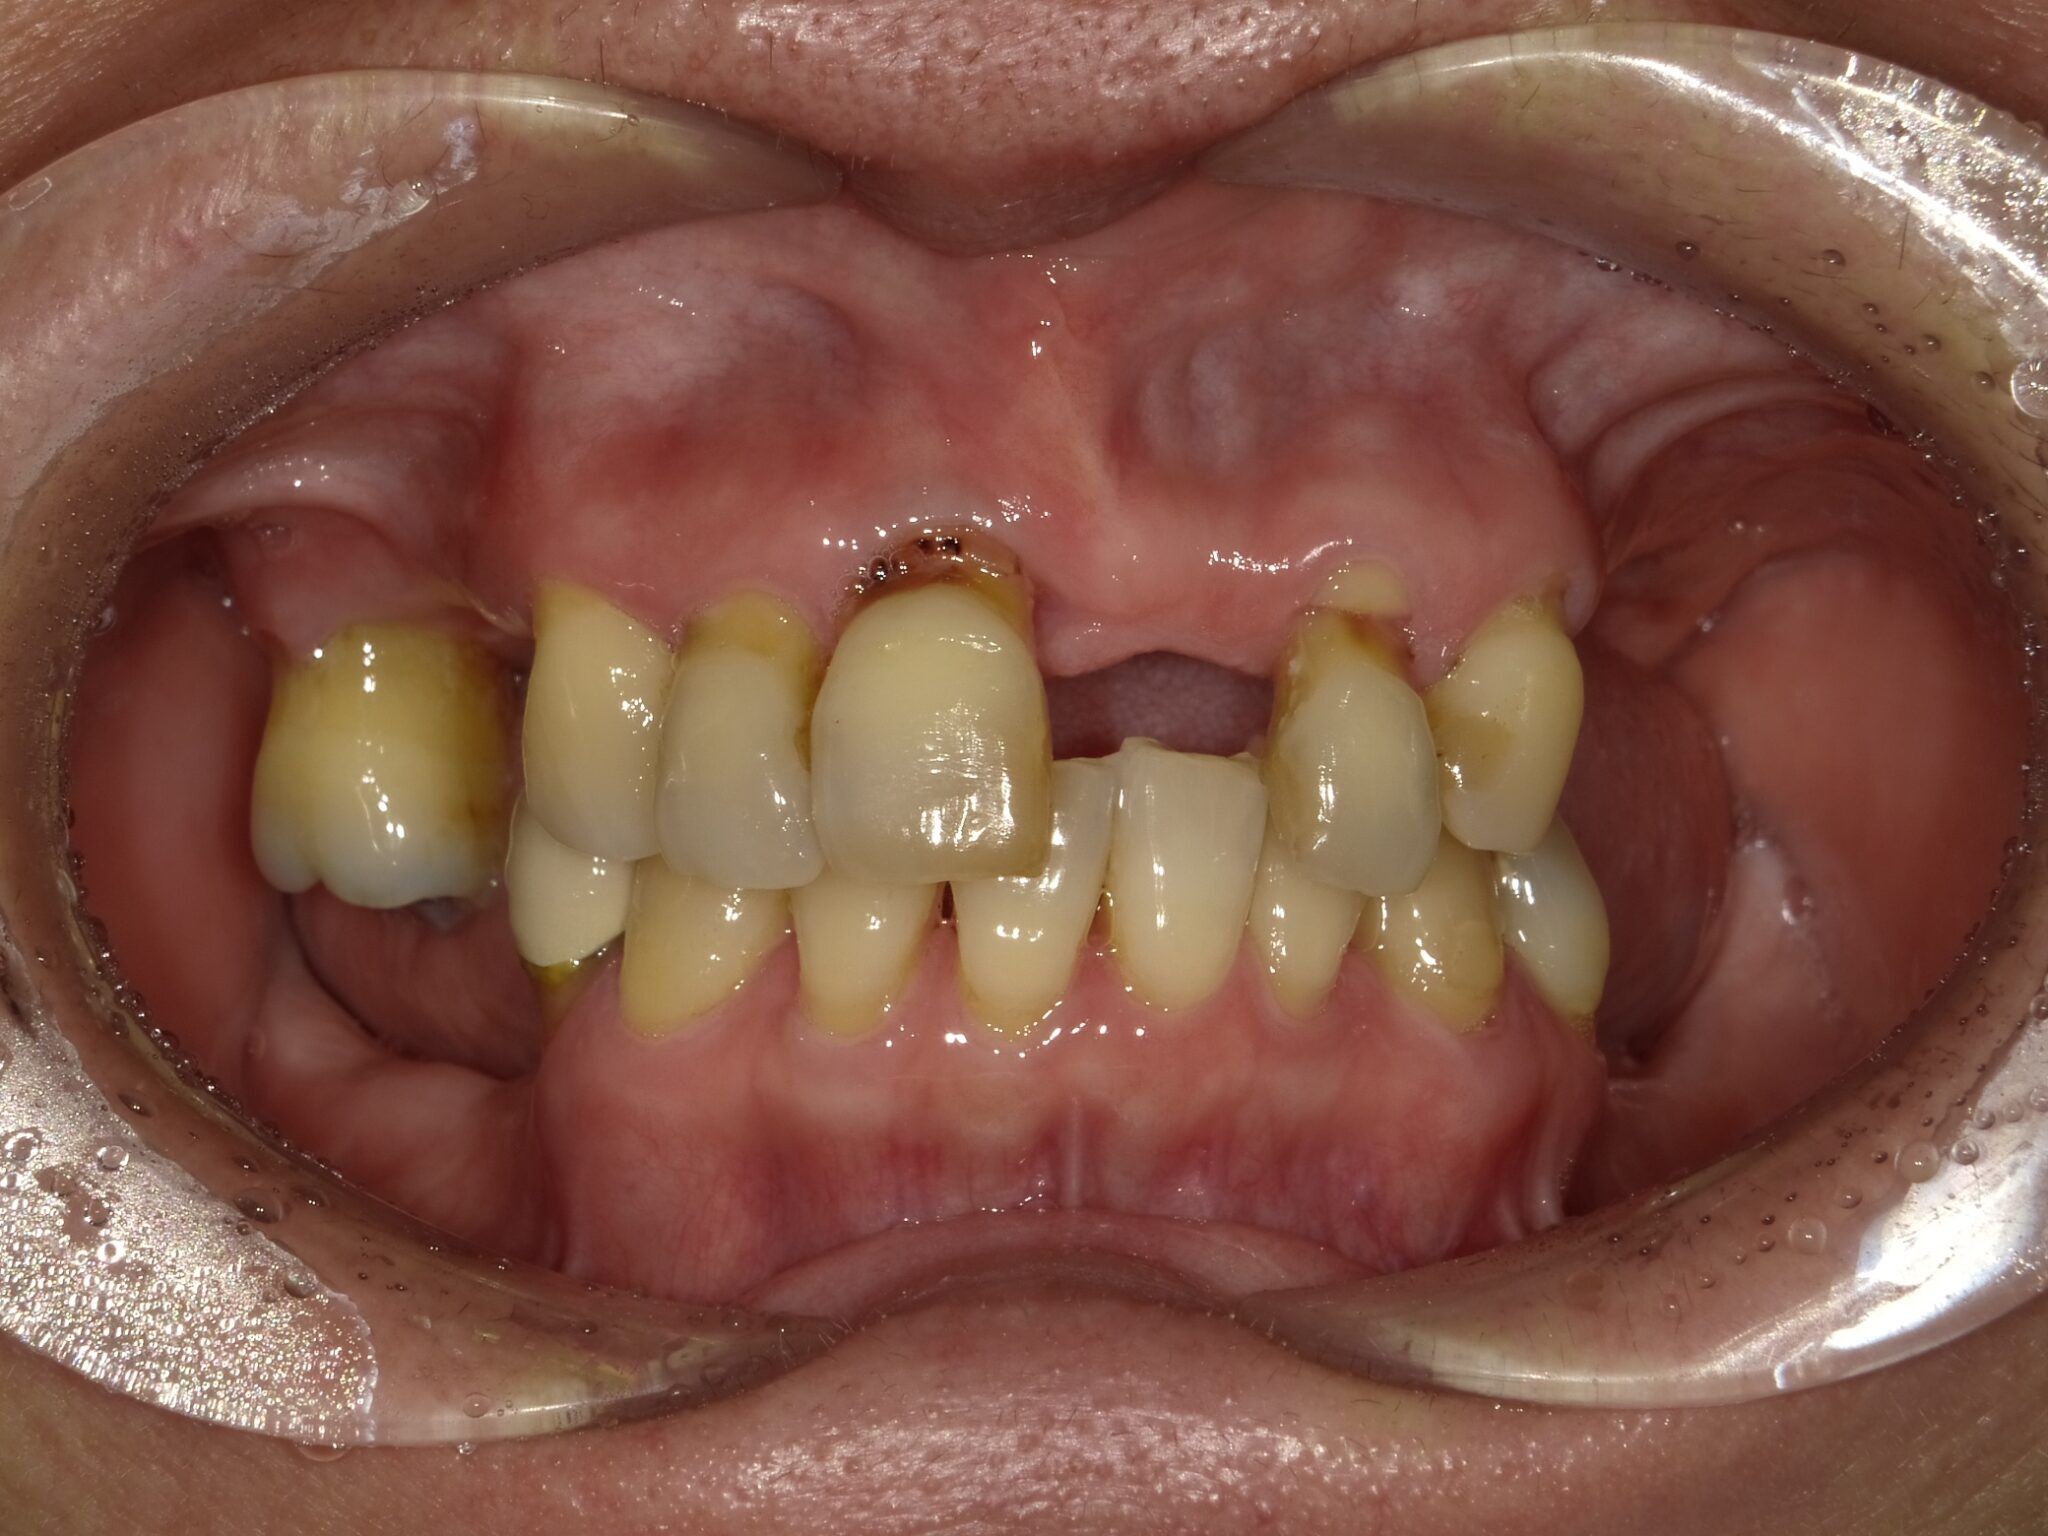

全顎治療症例

| 主訴 | 全体的に見た目を綺麗にしたい。奥歯でしっかり噛みたい。 |

| 診断名・ 主な症状 |

臼歯部欠損 |

| 治療内容 | インプラント埋入(左下5・6,右下5・6,左上4・6) サイナスリフト(左上4・6) ジルコニアBr(右上6−左上3) E –MAX CAD(右下4) セラミックインレー(左下4) |